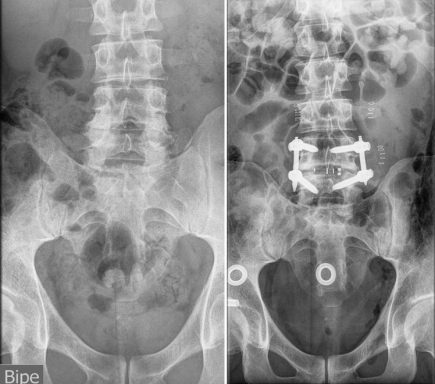

Me detectaron una gran herniación en L4-L5, y bastantes discos desgastados.

Cuando a pesar de la medicación, el deporte, y mi vida saludable, llegó un punto en el que ya no sentía alivio, decidí volver al traumatólogo para comprobar que la hernia no estaba pinzando demasiado la raíz, pero la sorpresa fue que en la RMN, se observaba la existencia bastante evidente de Romanus. Mucho más del que pueda verse en cualquier degeneración vertebral por el paso del tiempo.

La visita al reumatólogo no se hizo esperar y las siguientes pruebas, exámen de movilidad, Sacroileitis, (HLA-B27 negativo, que no quiere decir no padecer una espondiloartropatía) confirmaban el diagnóstico. Se trataba de Espondilitis Anquilosante. (Enfermedad con la que comparto iniciales)

Mi afectación consiste en dolor en columna cervical y lumbosacra, (Las sacroiliacas muy comprometidas) cadera, rodillas, tendones, muñecas, fatiga muscular y respiratoria, uveítis esporádicas, e inflamación intestinal y en consecuencia, sangrados.

Las vértebras L4-L5, totalmente colapsadas, y apófisis transversas impactando en la cresta iliaca, dieron el resultado final de una cojera permanente, por lo que me realizan una artrodesis lumbar con OLIF.